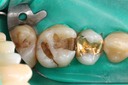

Kyle Chock #18 caries removal